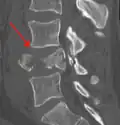

A burst fracture of L4 as seen on CT A burst fracture of L4 as seen on CT